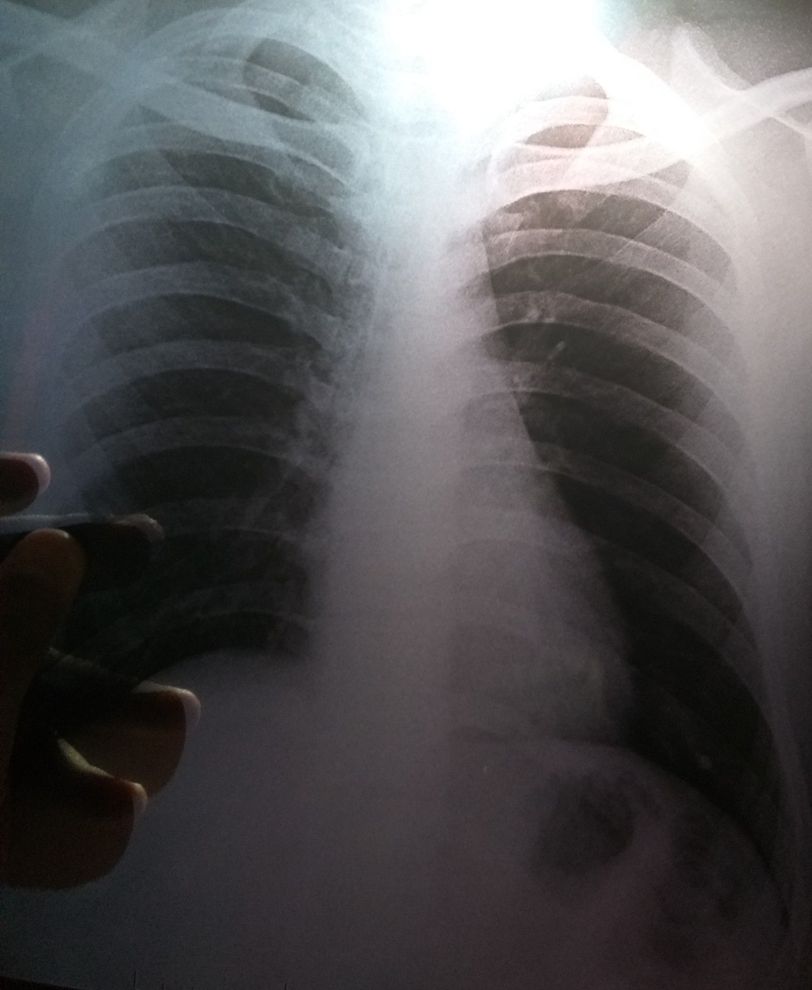

Left lower lobe consolidation....H/o - patient complaining bad odor sputum and mucus without cough from 1 year.... plz diagnose

Diagnosis

Xray

Pulmonary